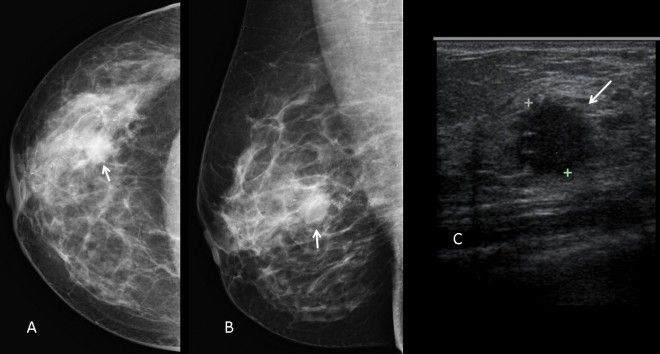

Ecografia mamară bilaterală evaluează starea de sănătate a sânilor, permițând vizualizarea și localizarea diverselor leziuni, cum ar fi: chisturi, noduli mamari, formațiuni tumorale nou apărute, ganglioni axilari. În urma examinării, primiți un buletin ecografic cu diagnosticul clinic și stadializarea după scorul BIRADS, importantă pentru urmărirea pe termen lung a leziunilor existente.

Mamografia este cea mai importantă procedură imagistică pentru detectarea și diagnosticarea cancerului de sân. Scopul general este de a permite tratamentul precoce al cancerului de sân, de a îmbunătăți ratele de supraviețuire și de a reduce nevoia de tratament agresiv, cum ar fi mastectomia , în era actuală a terapiilor moderne.

Dacă vi se cere ,dupa mamografie ,să faceți o ecografie , acest lucru nu înseamnă că aveți cancer.

Acesta a doua examinăre, necesita confirmarea tipului de leziune descoperita mamografic, aprecierea vascularizatiei si structurii acesteia,din dorinta de a avea certitudinea ,in a afirma, că nu aveți cancer/leziune suspecta de cancer!

Mai puțin de 10% dintre femeile reevaluate ecografic post mamografie,sunt diagnosticate cu cancer!